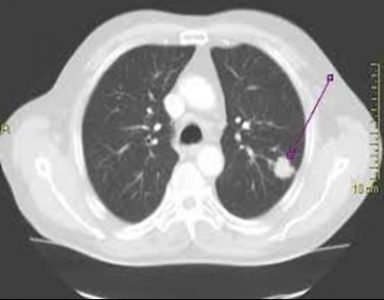

Ιδανικά παραδείγματα για τον RADIAL ΕΝΔΟΒΡΟΓΧΙΚΟ ΥΠΕΡΗΧΟ

Είναι η τελευταία λέξη της τεχνολογίας για τη βιοψία μονήρη όζου (βλάβη κάτω από 3 cm) ή μάζας στην περιφέρεια του πνεύμονα (κάτω από 3cm). Γίνεται με μέθη, όπως η γαστροσκόπηση, διαρκεί το μέγιστο 20 λεπτά και διενεργείται ταυτόχρονα και ταχεία βιοψία, οπότε εξασφαλίζεται άμεσο αποτέλεσμα.